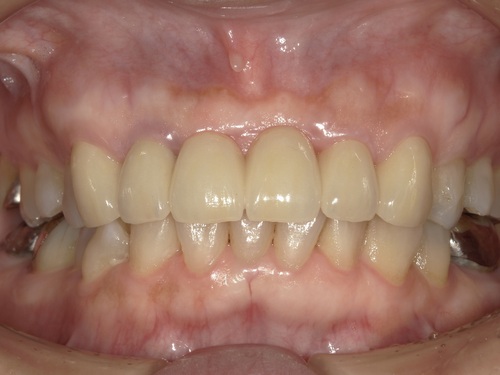

こちらが初診時のレントゲンとお口の写真になります。

右上の1番目の歯がすでになく、右上の2番目と左上の1番目の歯でブリッジが入っている状態です。ブリッジは、他の歯の色に比べ、白く不自然な色となっています。さらに、左上1番目の歯茎が腫れてしまっているのが良くわかります。

適合・色合い・噛み合わせに問題がないことを確認し、歯科用セメントでしっかりとセットしました。術前と比較して色も自然でとても美しい仕上がりかと思います。

初診時にはインプラント治療にするかブリッジ治療にするか大変悩まれておりましたが、綺麗なブリッジが入って、患者様は今回の治療に大変満足されております。また保険外治療で高額な治療とはなりましたが、とても綺麗な歯が入ったと『ジルコニアセラミックにして良かった』とおっしゃられておりました。